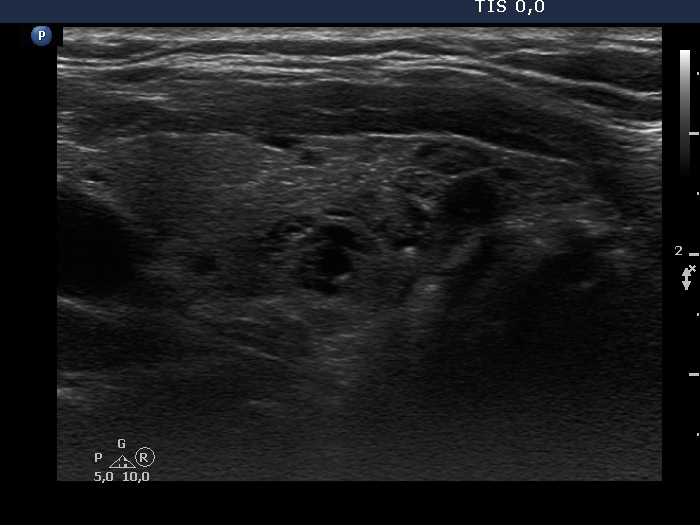

Consecutive patients with the final diagnosis of Hashimoto's thyroiditis - case 38 (1617) (ultrasonographic picture 6)

Left lobe, another longitudinal scan.